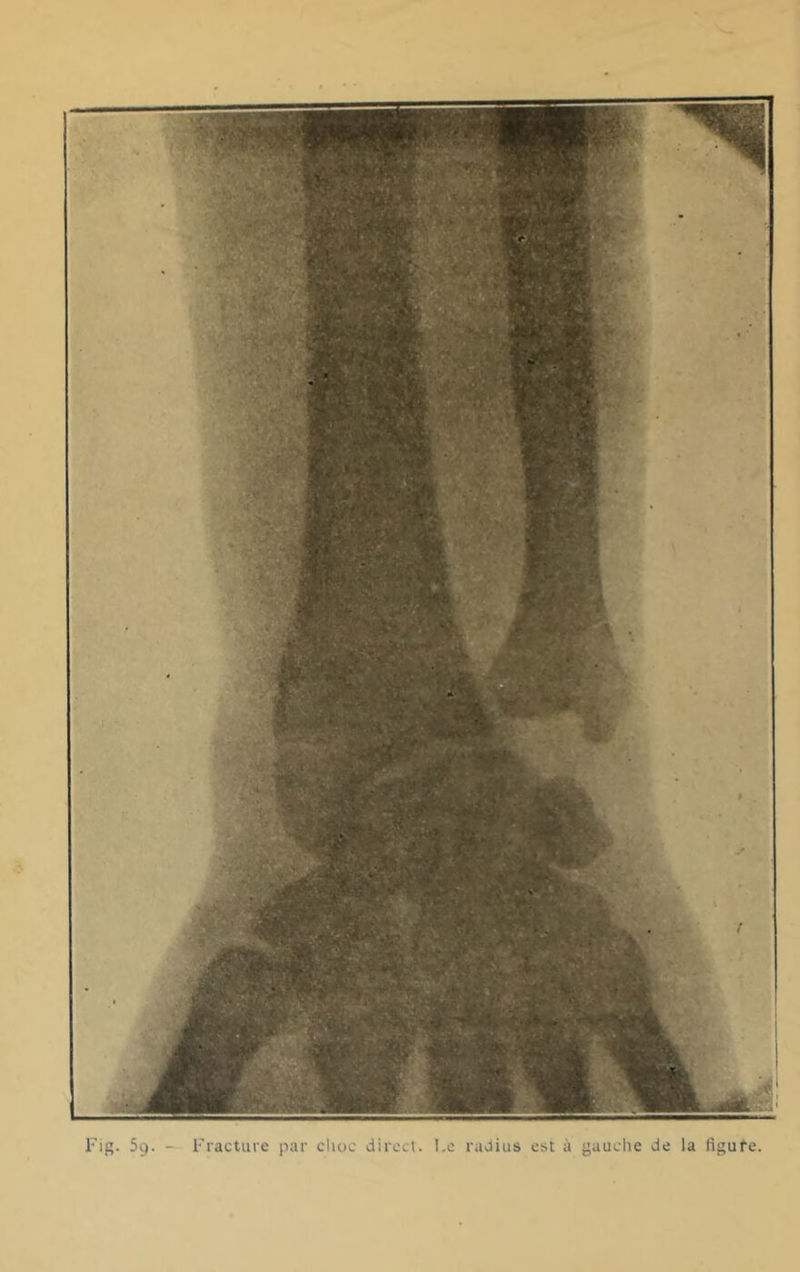

208/236 page 192